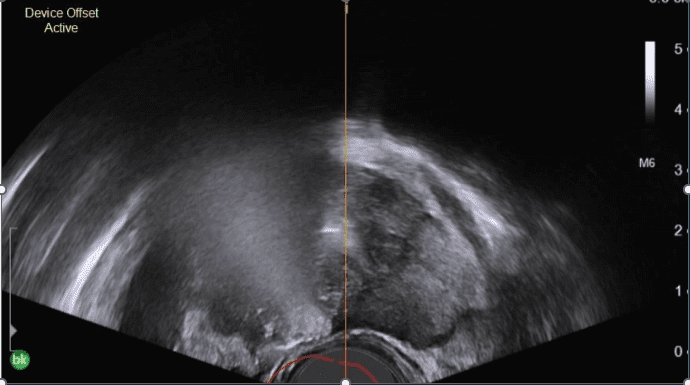

VAPOR 2 is a novel, multi-center trial using a transurethral thermal water vapor device (Vanquish) to manage localized intermediate-risk prostate cancer. Enrollment is complete and the 235 patients will be followed for 5 years.

Data published on the first 110 patients with 12-month follow-up demonstrated that:

- 91% clearance of targeted MRI visible ≥ Grade Group 2 (GG2) disease following a single treatment

- Ability to treat anywhere in the prostate

- No device-related serious adverse events